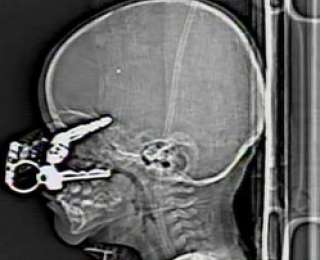

Случай с 20-месячным ребенком Николя Холдманом (2008 год) также можно назвать чудом, так как малыш умудрился упасть на ключи от авто, принадлежащих его родителям. Не смотря на то, что ключи угодили ему прямо в мозг, ребенок остался жив.